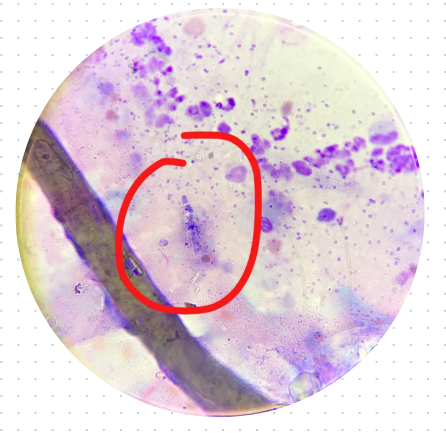

一、猫癣的元凶:犬小孢子菌

猫癣的致病菌并非单一品种,但90%以上的病例由犬小孢子菌引发。这种真菌的适应性极强:

▷能在宿主毛发中形成孢子链,单根毛发可携带200-400个孢子

▷在干燥环境中存活长达18个月

▷对温度耐受范围广(4-40℃),常规日晒难以灭活

更危险的是,犬小孢子菌的孢子表面具有疏水蛋白,使其能轻松附着在纺织品、家具等日常物品表面。实验室研究证实,受污染梳子上的孢子存活率在30天后仍保持62%。